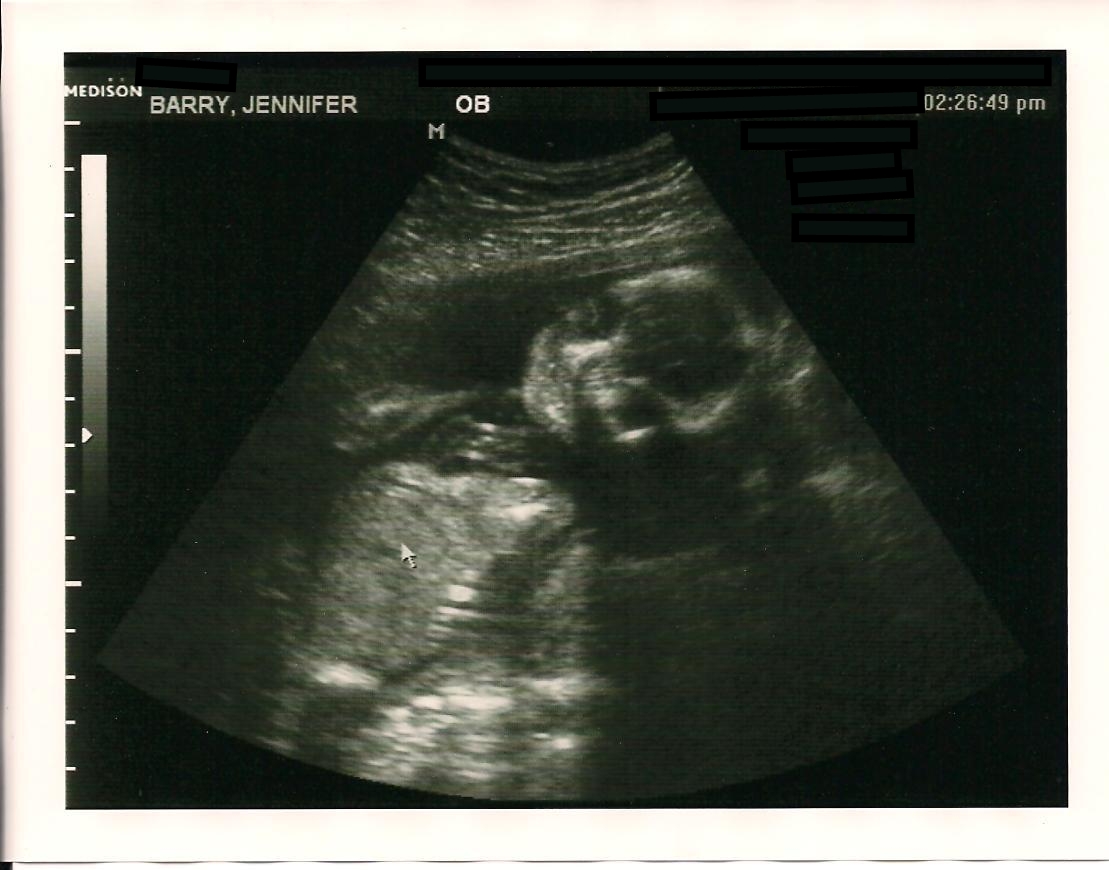

When we got to the doctor's office we were both so excited to find out if we would be having another precious girl or an all new to us little boy. It didn't take them long to call our names and we headed back to the ultrasound room. When I got situated, our sweet technician put the magic wand on my belly and announced within five seconds...."It's a boy." Shawn and I were both shocked. We'd told her before hand that we wanted to know the gender, but honestly I had no idea she would be able to tell that quickly. Ha! I guess our little guy isn't shy at all. =) She showed us the four chambers of his tiny beating heart, his stomach, lungs, and his little skull. She said that everything looked great and I think Shawn and I were both so relieved to hear that and to see his sweet little arms, legs, toes, and fingers too! It was really precious to watch him move his sweet little self around!!!

Here are a few pictures of our little man!

He looks like skeleton man here, but I can still see the sweet face of my baby boy!